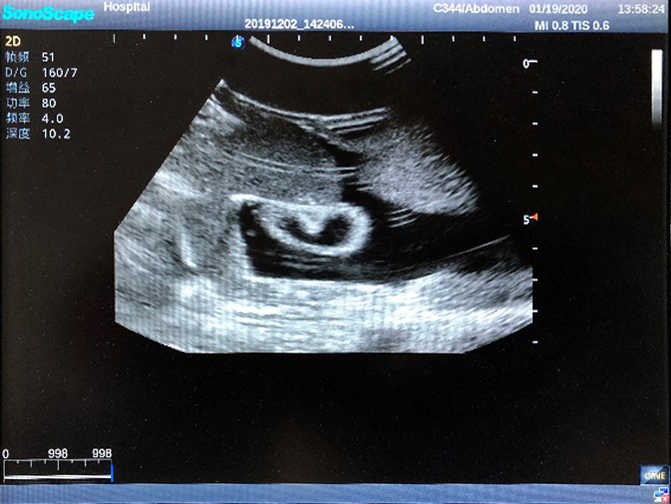

2) High quality ultrasound image with clear structures like gallbladder, liver, intestines, arteries and veins etc.

5) Normal & pathological ultrasound live and intestine models inside